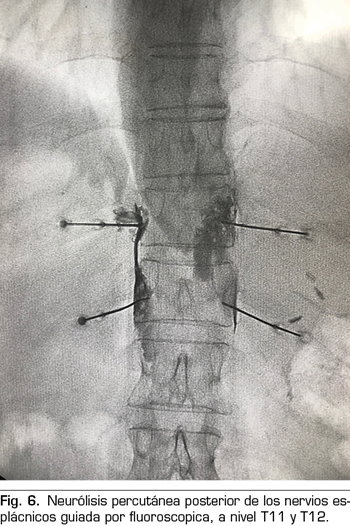

Técnica percutánea

Se realiza mediante un abordaje posterior retrocrural, normalmente guiado por fluoroscopia (Figura 6). Las lesiones pueden llevarse a cabo mediante radiofrecuencia convencional o utilizando agentes neurolíticos como en el plexo celiaco.